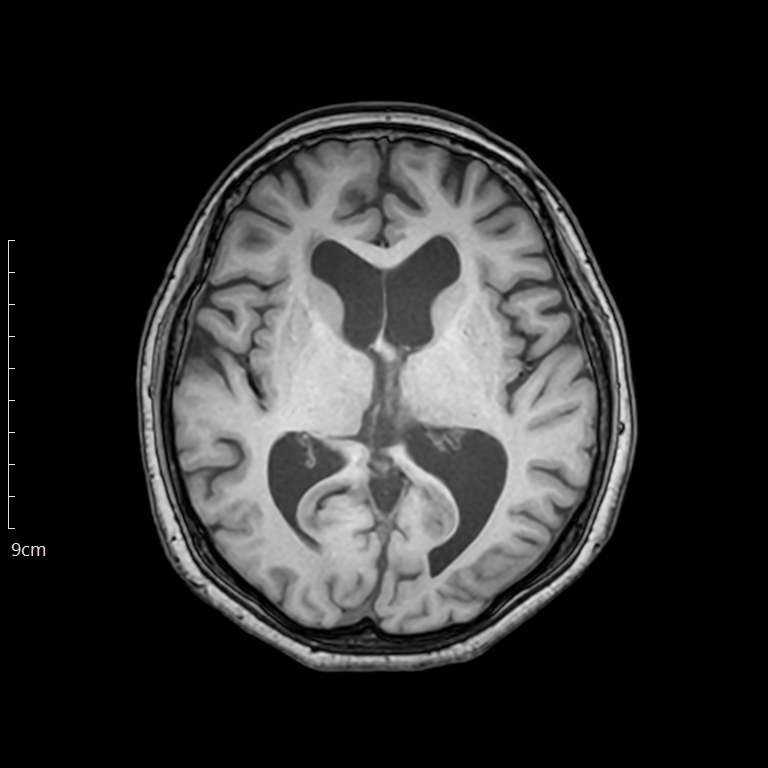

MRI(Magnetic Resonance Imaging)는 X-ray를 사용하지 않고, 강한 자기장과 라디오파를 이용해 인체 내부 영상을 만드는 검사입니다. 특히 뇌, 척추, 관절, 인대, 근육, 연부조직처럼 구조가 섬세한 부위를 정밀하게 확인하는 데 탁월합니다.

- 주요 사용 분야: 뇌종양, 디스크, 관절질환, 연골 손상, 심혈관 질환 등

- 검사 시간: 평균 20~40분 (긴 경우 1시간 이상)

- 방사선 노출: 없음